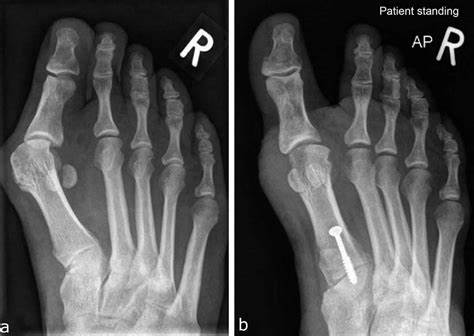

일단 치료 방식을 결정하기 전에, 엑스레이로 '무지외반증' 정도를 평가합니다.

기본 엑스레이를 통해 각도를 측정하는데 동일한 AP view 에서 주로 평가합니다.

1. HVA : Hallux Valgus Angle < 15도 이하 정상

2. IMA : Inter Metatarsal Ange < 9도 이하 정상

3. DMAA : Distal Metatarsal Articular Angle < 10도 이하 정상

선을 그을때 대부분 중족골의 중심인 선과 근위 족지의 각을 이용하도록 합니다. 원위 중족골 관절각도(DMAA)는 중족골 선의 90도인 선과 근위 족지의 관절에서 이은 선의 두 각도를 의미합니다. DMAA 가 증가되어 있으면 연부조직의 재건을 하는 것이 좋습니다. (DMAA 가 20도 이상인 경우에는 distal + Akin, distal biplane chevron, Double (distal + porx) 등 복합교정을 이용해야하고, 단순한 교정으로는 교정이 어렵습니다. )

위의 정상 수치보다 크게 되면 무지외반증으로 진단이 가능합니다.

수술의 경우 변위 정도에 따라 Chevron, Distal softh tissue, Akin procedure 등을 시행해 볼 수 있습니다.

중등도 이상에서는 Proximal crescentic osteotoma, Mitchell procedure 등을 시행합니다.

아주 심한 변형에서는 Joint fusion 을 시도해 볼 수 있습니다.